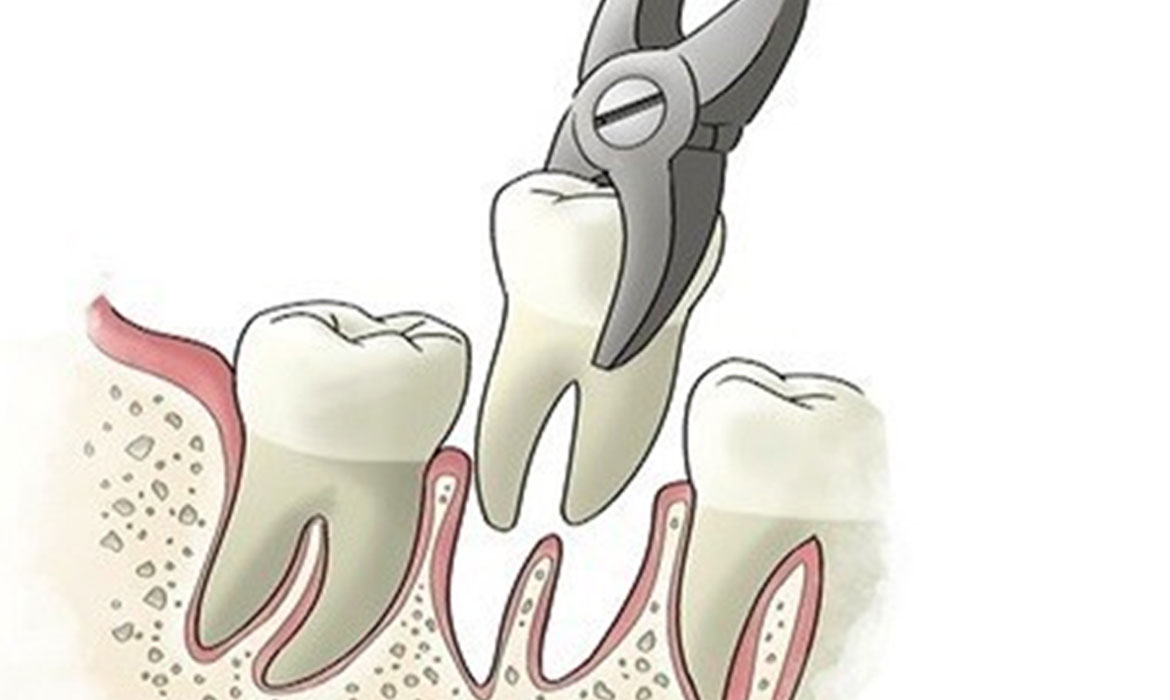

- in ultima analisi può esserci la perdita dell’elemento dentario.

Ad esempio potrebbe pianificarsi una estrazione semplice al secondo trimestre con annesso dente finto provvisorio per poi rimandare impianto o ponte definitivo dopo la gravidanza.